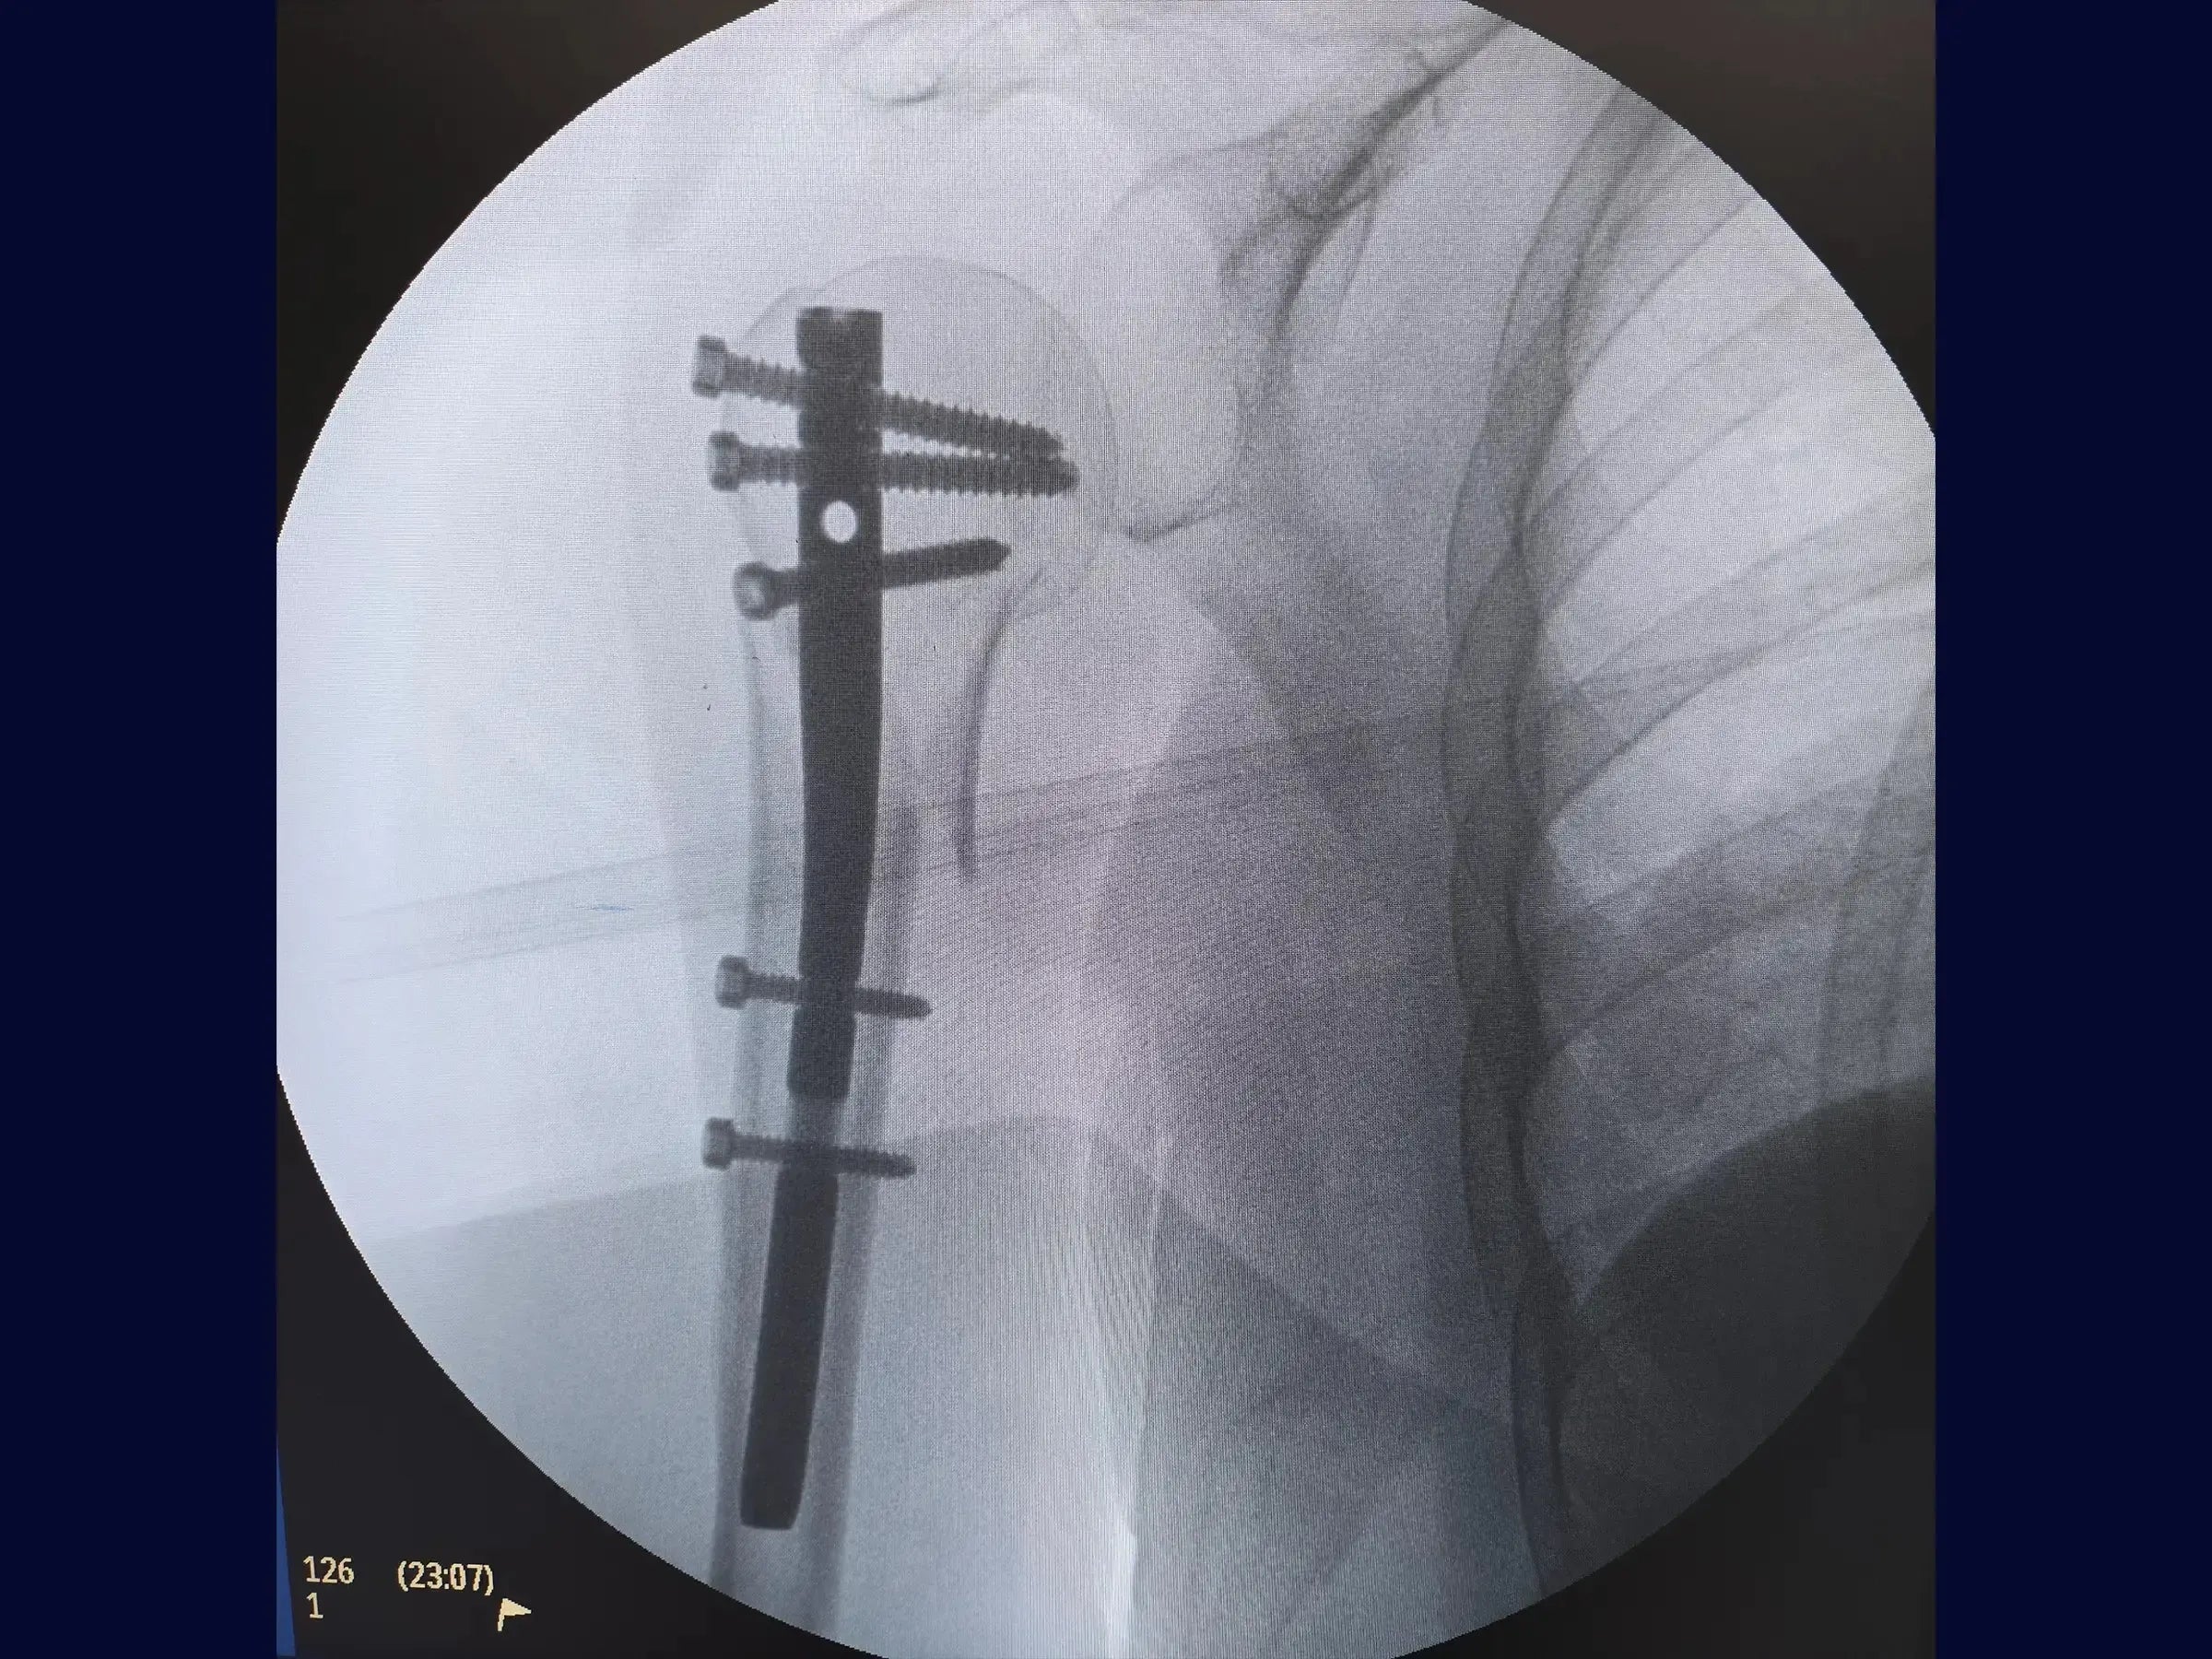

- Systematized Percutaneous Blocking: Protocols for safe and effective insertion of proximal and distal locking screws.

- Non-Cannulated Rod Insertion Technique: Step-by-step approach for opening the medullary canal and manual introduction of the rod under fluoroscopic control.